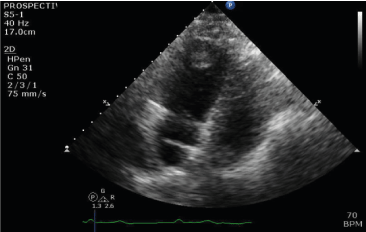

Intra-operative resection of the RV mass revealed a 2.2 cm x 1.7 cm x 1.5 cm focally disrupted tan-pink soft tissue that weighed 2 grams (Figure 2). Subsequent pathological analysis of the tissue was consistent with papillary endothelial hyperplasia (PEH).

Figure 2.Right ventricular mass

Supplemental oxygen therapy via nasal cannula was administered and the patient was admitted to the intensive care unit. Anticoagulation with intravenous heparin was initiated. Various treatment options of a saddle PE with hypoxia and evidence of right heart strain were considered such as systemic thrombolytic therapy, catheter directed thrombolysis or thrombectomy and surgical embolectomy. In order to address the RV mass that was concerning for a thrombus in transit in the setting of a high thrombus burden including DVT and a large saddle PE, the option of surgical embolectomy was chosen by a multidisciplinary team that included Cardiology, Intensivist and Cardiothoracic surgery services. Successful surgical embolectomy of the saddle PE measuring 32 cm x 1.2 cm was performed (Figure 3). Primary closure of the secundum atrial septal defect was also performed. Intraoperatively, the RV mass was found intertwined with the trabeculations and chordae of the tricuspid valve (Figure 4). It was 2.2 cm x 1.7cm x 1.5 cm in size and with a gross appearance of a myxoma, but the pathological evaluation was consistent with papillary endothelial hyperplasia (Figure 5). Patient recovered well and was discharged on apixaban for treatment of VTE.